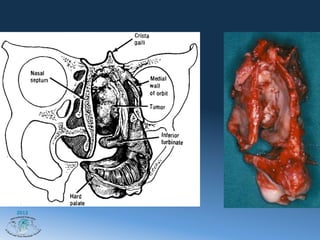

Мукоэпидермаоидная карцинома слезного

мешочка

Моноблочная резекция

2012

Мукоэпидермаоидная карцинома слезного мешочка Моноблочная резекция 2012